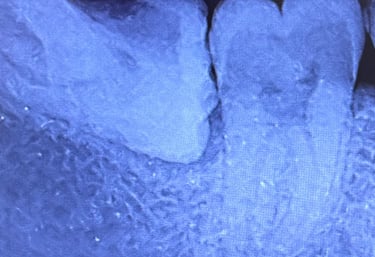

Prima...

...e dopo il trattamento